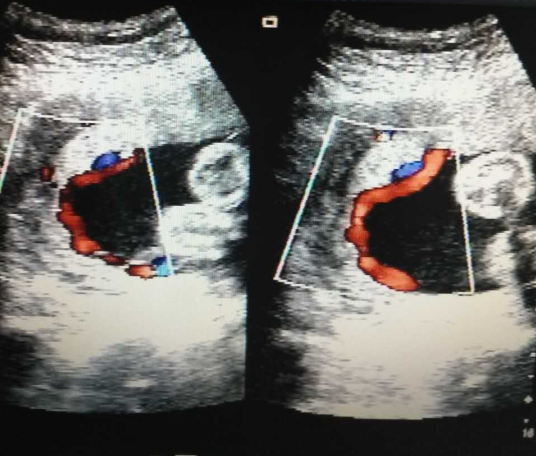

近日,超声室用GE Voluson E10超声仪器诊断一例中孕期帆状胎盘。

徐女士,38岁,孕26周,自怀孕以来,仅于早孕期在我院做过一次超声检查,再次来院产检,超声报告见:胎儿脐带胎盘插入点沿胎膜走行21mm后进入胎盘边缘处,超声诊断为脐带插入点异常,考虑帆状胎盘可能性大。随后,经来我院坐诊的省级医院超声专家会诊,证实我院诊断。

帆状胎盘指脐带附着在胎盘之外的胎膜上,脐带的血管分散成数条分支成扇形分布走行,最终连于胎盘边缘部分,形成一膜状结构,如帆船的帆布,称之为帆状胎盘。这些血管极易发生破裂,特别是当这些血管分支位于胎先露下方,跨越或接近宫颈内口时。当血管受压或胎膜破裂时血管撕裂,可造成胎儿缺氧或急性失血、胎儿失血性休克,因此胎儿死亡率极高。